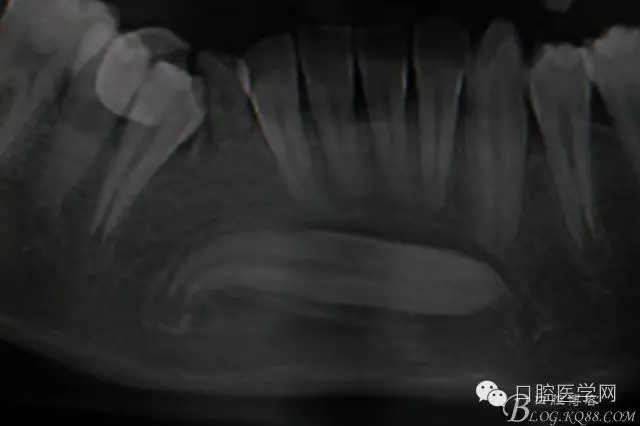

橫位埋伏3的取出術(shù)